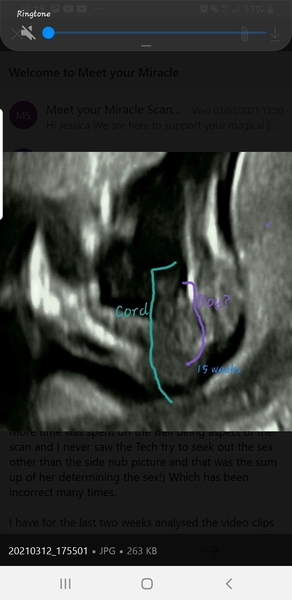

@HistoriaTrixie Hi, what do you think of mine please.. would really appreciate your opinion..

All images are from exactly 15 weeks...

MamaJ8 · 14/03/2021 20:47

I also have think that there is a shape that looks like a scrotum and looks similar to OP's?

What do you think?😊

@MamaJ8 I am so sorry, I just saw this!! It looks like a boy to me though I'm not nearly as sure as I was with the last one.